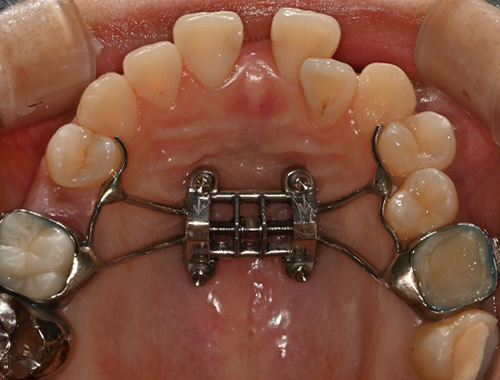

비수술 악궁확장 치료 MARPE (Miniscrew-assisted rapid palatal expansion)

CASE 01

확장 전

확장 후

CASE 02

이지민 원장은 성인 비발치 교정의 핵심인 비수술 악궁 확장 가능성을, 직접 연구한 논문 결과를 바탕으로 사전에 정밀 분석·예측합니다.